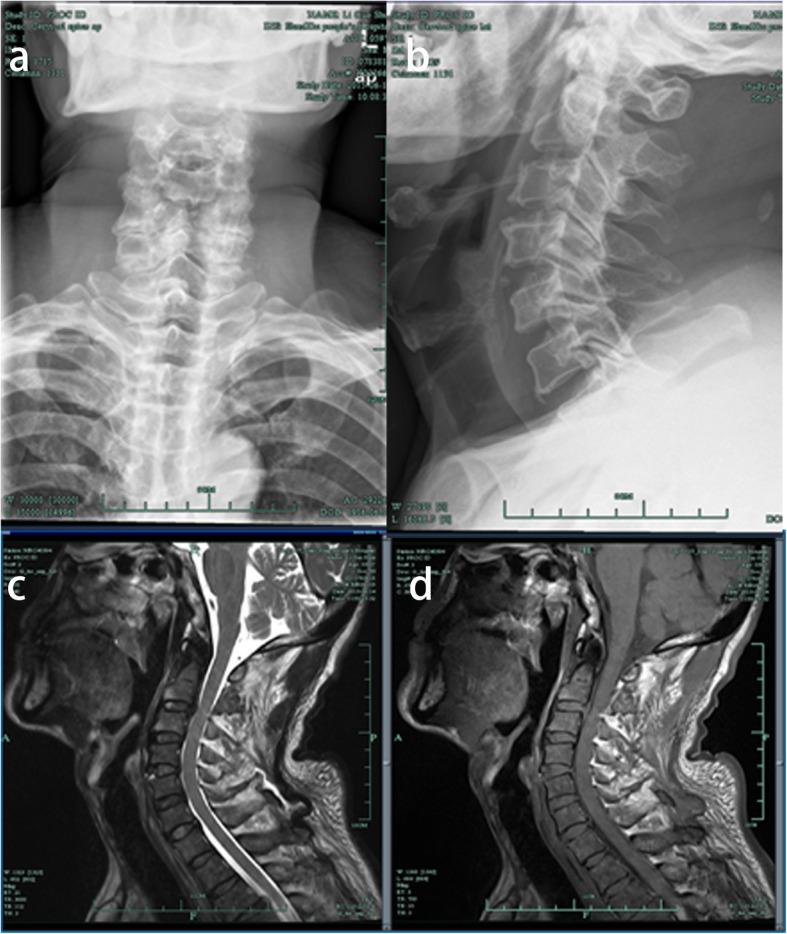

A 63 year old male patient suffered from cervical spine hyperextension after trauma accompanied by numbness of the hands and decreased muscle strength in both upper limbs. Anterior cervical fusion surgery was performed in our hospital, after which the patient's upper limb numbness disappeared and muscle strength returned to normal. In the fifth month after surgery, the patient developed a sore throat and dysphagia. Symptoms gradually worsened, and the patient was hospitalized four times, subsequently undergoing tracheotomy, internal fixation removal, and polypectomy. The patient's pronunciation, breathing, and swallowing functions returned to normal, and the incision healed. After a one-year follow-up, the polyp did not recur.